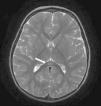

El paciente es hospitalizado y realiza dos convulsiones en racimos durante las primeras 36 h. Como único hallazgo microbiológico, se aísla antígeno de rotavirus positivo en heces. El registro electroencefalográfico fue normal. Por repetición de las crisis, se realiza una resonancia magnética (RM) cerebral, observándose una lesión aislada hiperintensa en T2 y difusión con restricción de la misma bien delimitada de 12×4mm de diámetro, localizada en la porción central del esplenio del cuerpo calloso (figs. 1 y 2). No capta contraste ni produce efecto masa sobre estructuras adyacentes.